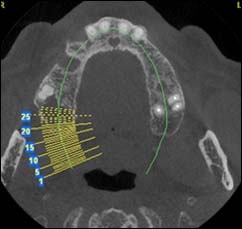

EXAMENS TOMOGRAPHIES VOLUMIQUES TYPE SCANNER OU CÔNE BEAM :

Dernière technologie à notre disposition, cette technique permet de voir en 3 dimensions des images de votre bouche et de mettre en évidence des pathologies ou des anomalies que les autres techniques ne permettent pas d’objectiver.

Coupe axiale